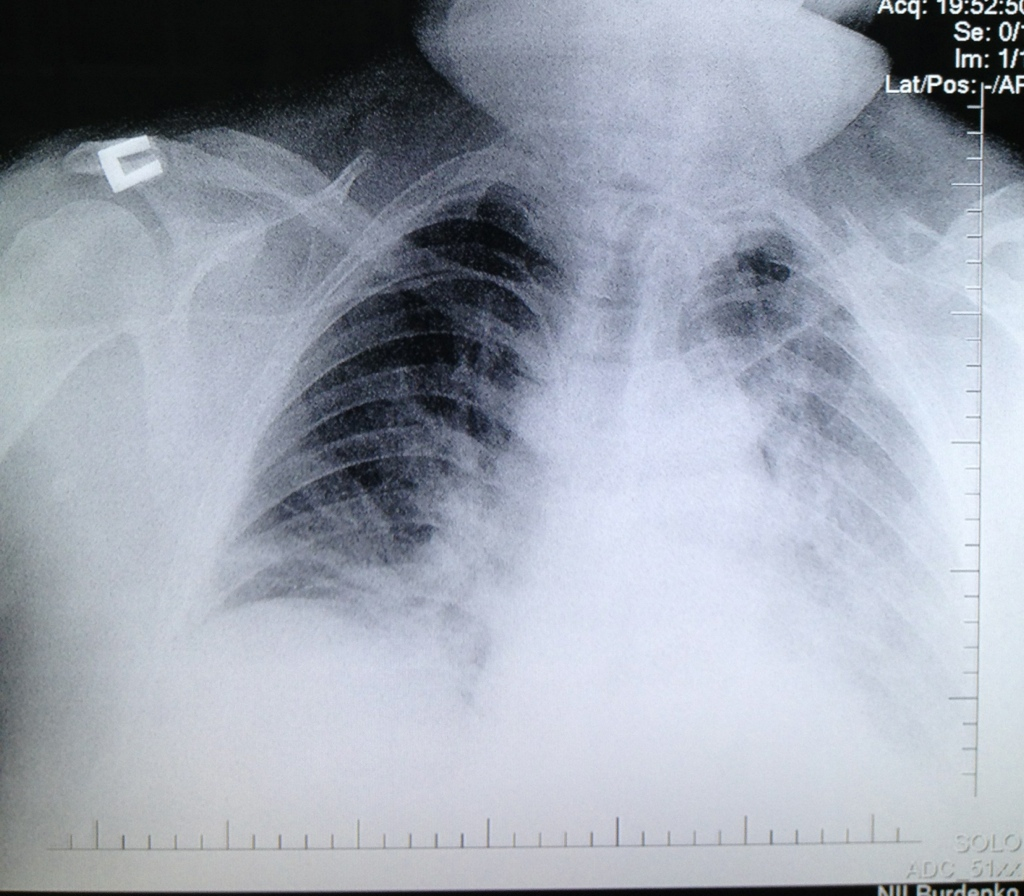

С первых суток пребывания в Институте у пострадавшего отмечались гипертермия до 39,0º С, повышение С реактивного белка до 125 мг/л, лейкоцитоз- 22.89 х 10 000000000/л (норма- <5 мг/л и 4.0-10.0 х 10 000000000/л соответственно) со сдвигом лейкоцитарной формулы влево, рентгенологические признаки аспирационной пневмонии (рис. 2).

Рис. 2 Рентгенограмма органов грудной полости пациента К., 42 года